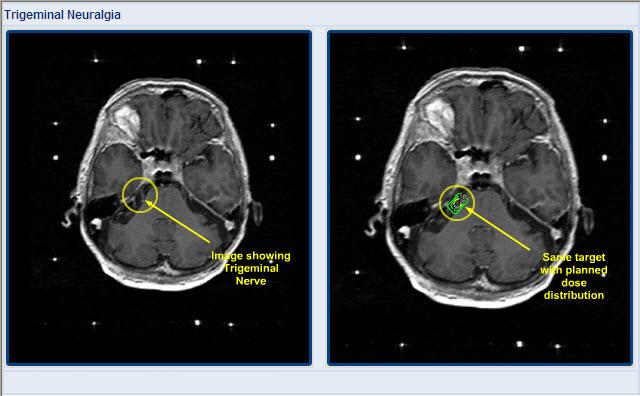

Gamma Knife radiosurgery is a major advance in the treatment of trigeminal neuralgia, an otherwise agonizing condition characterized by paroxysmal triggered face pain. Gamma Knife radiosurgery not only relieves the pain as well as the other neurosurgical forms of treatment, but it does so with fewer complications.

Excellent or good pain relief occurs in approximately 90 to 95 percent of patients. Onset of pain relief may occur one day to three months after the procedure. More than half of patients will experience pain relief within four weeks. Recurrent pain occurs within three years in 5 percent of patients. Patients with TN and multiple sclerosis also may be helped by the procedure.

Major complications have not been reported. Additional numbness in the face or new facial sensations occur in less than 5 percent of patients.